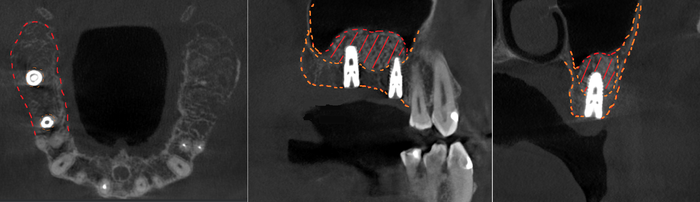

Контрольная ортопантомограмма:

Прицельный снимок: